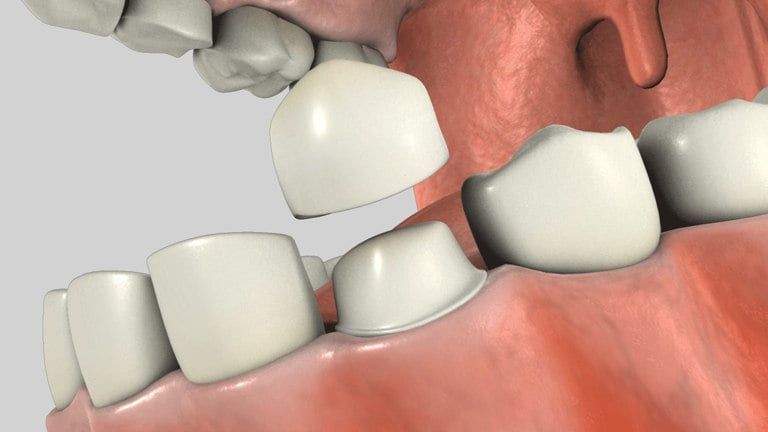

Full Porcelain Crowns

These are very aesthetic, bonded crowns. They are mostly used for front teeth because they are the most natural looking type of crown and are often used in "cosmetic" dentistry.

There are many types, but they all have a common feature - no metal. They can occasionally break, but dental technology has advanced far enough to make them quite strong.